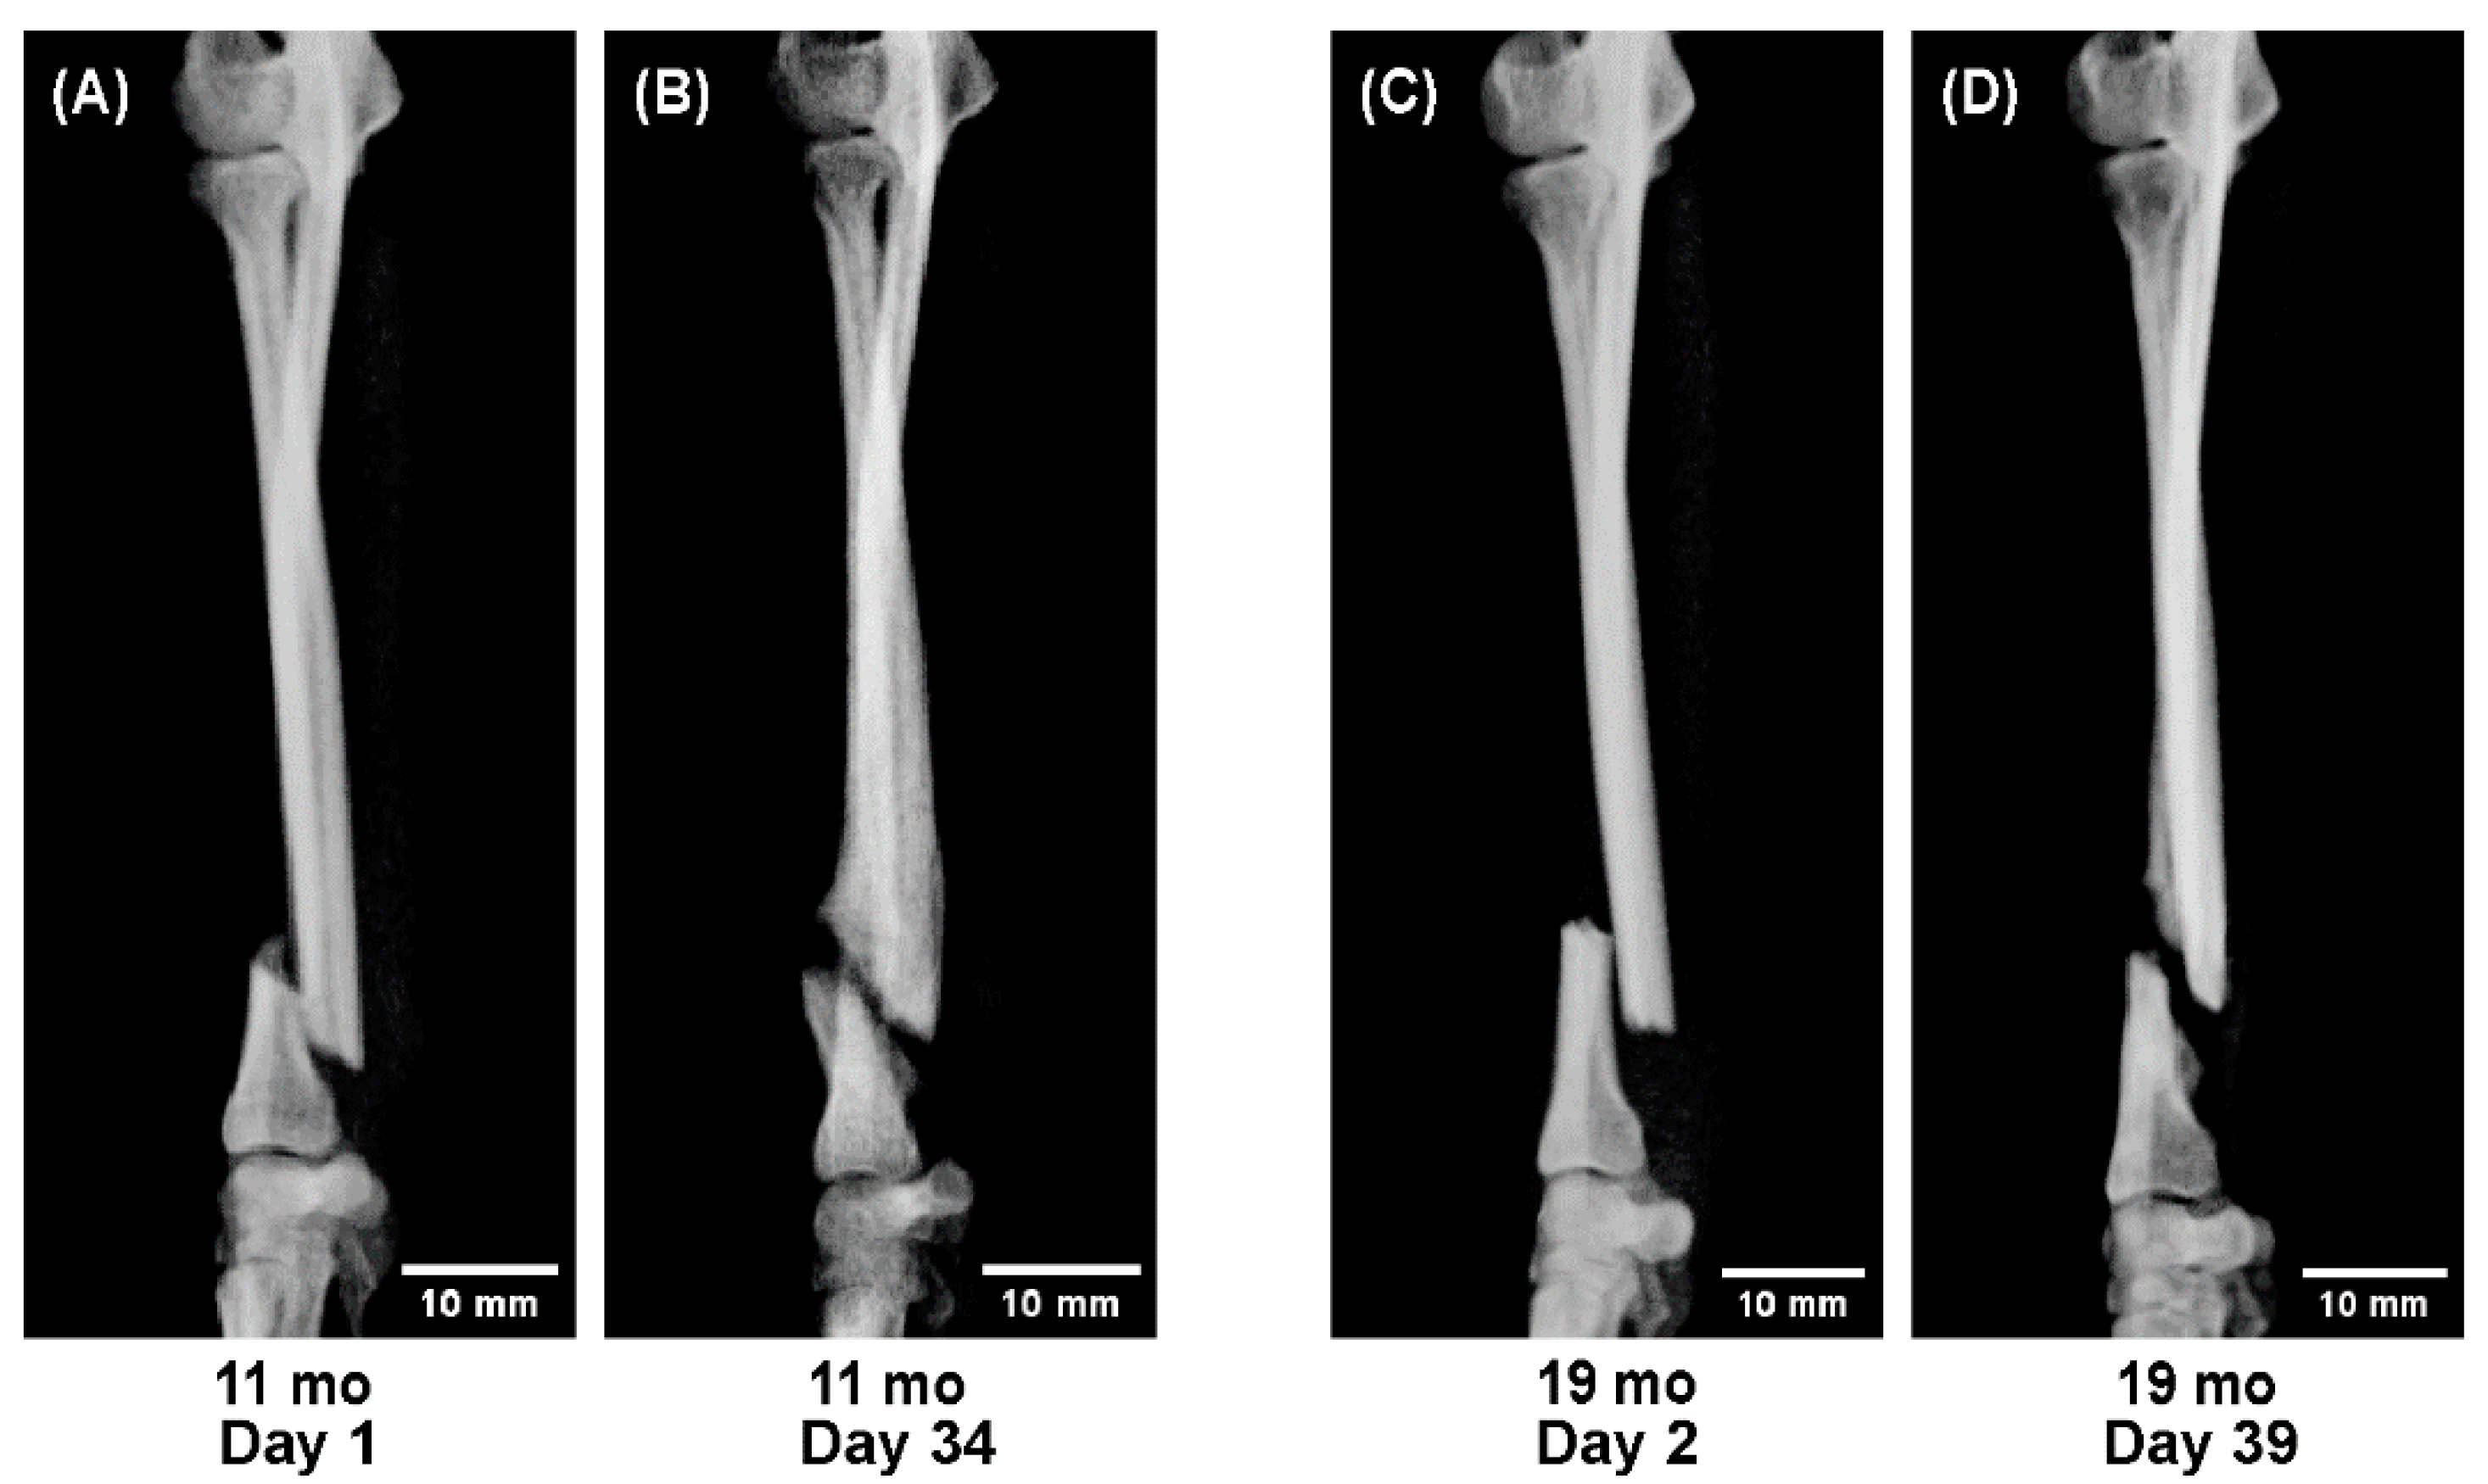

- A 5-month-old dog showing rapid callus proliferation (juvenile stage),

- Dogs aged 11 and 19 months showing reduced callus formation (adolescent stage), and

- Dogs aged 2 and 9 years showing stable but slower consolidation (adult to senior stage).

- A sequential radiographic series of a 5-month-old dog,

- Comparative observations between 11 and 19 months, and

- Between 2 and 9 years.

3.5. Radiographic Comparison by Age